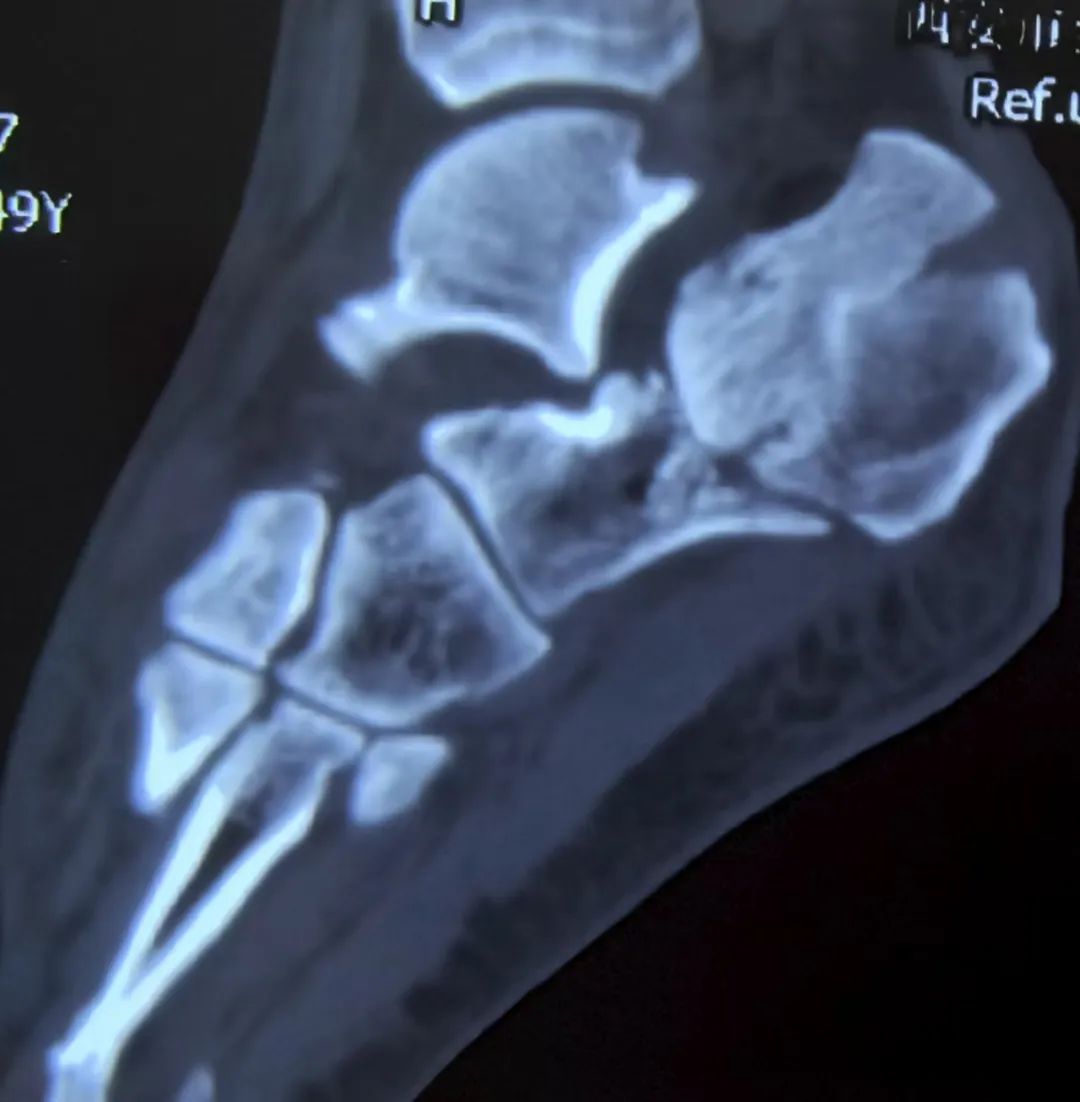

术前对骨折块以及骨折线的方向的了解是非常重要的,CT是很好的工具。

CT可以很好的显示嵌插骨块的位置(这个对复位至关重要)

这是一例比较复杂的跟骨,合并舌型骨折块,同时内侧嵌插严重,关节面塌陷。